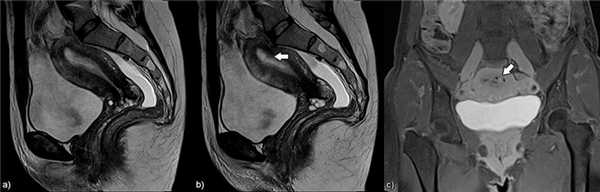

Рис.3: Схематическое изображение и сагиттальные T2-взвешенные изображения нормальной постпубертатной матки (а), диффузного аденомиоза (b), фокального аденомиоза (с).

а) эндометрий однородно гиперинтенсивный, тонкая переходная зона имеет низкую интенсивность сигнала, наружный миометрий имеет промежуточную интенсивность сигнала; b) и с) аденомиоз матки с гипонтенсивным диффузным и фокальным расширением переходной зоны.

Рис.5: Фокальный аденомиоз: а) сагиттальные T2, b) аксиальные T2 , с) аксиальные T1 3D FS изображения, показывающие фокальное асимметричное утолщение переходной зоны, образующее плохо отграниченную область с низкой интенсивностью сигнала, наличием в структуре мелких гиперинтенсивных на Т2 и Т1FS включений, представленных мелкими кровоизлияниями.